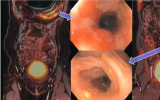

PET/MRE改善克羅恩病的檢測

根據4月19日在檀香山舉行的美國倫琴射線學會(ARRS)年會上的一份報告,同時進行PET/MR腸道造影(MRE)可以提高對活動性炎癥性克羅恩病的檢測。 2023-05-03